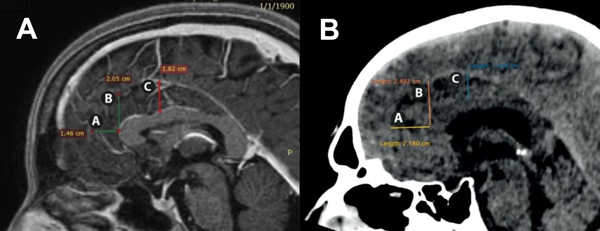

Las mediciones se realizaron en cortes sagitales en RM (Philips Achieva de 1.5T con los siguientes parámetros de adquisición de las imágenes de la secuencia 3D T1: TR = 7ms, TE = 3ms, ángulo de inclinación = 8, matriz de adquisición = 256x222, espesor de corte = 1 mm, tamaño de vóxel = 1x1x1 mm) y TC (Toshiba Lightning 16 Achilles con cortes finos de 0,5 mm) de cerebros normales (Figura 2). Las mediciones fueron realizadas siempre por las mismas personas y siempre con la misma angulación de los cortes, para evitar sesgos.

Figura 2:

A: Distancias A, B y C en resonancia magnética en plano sagital.

B: Distancias A, B y C en tomografía computarizada en plano sagital